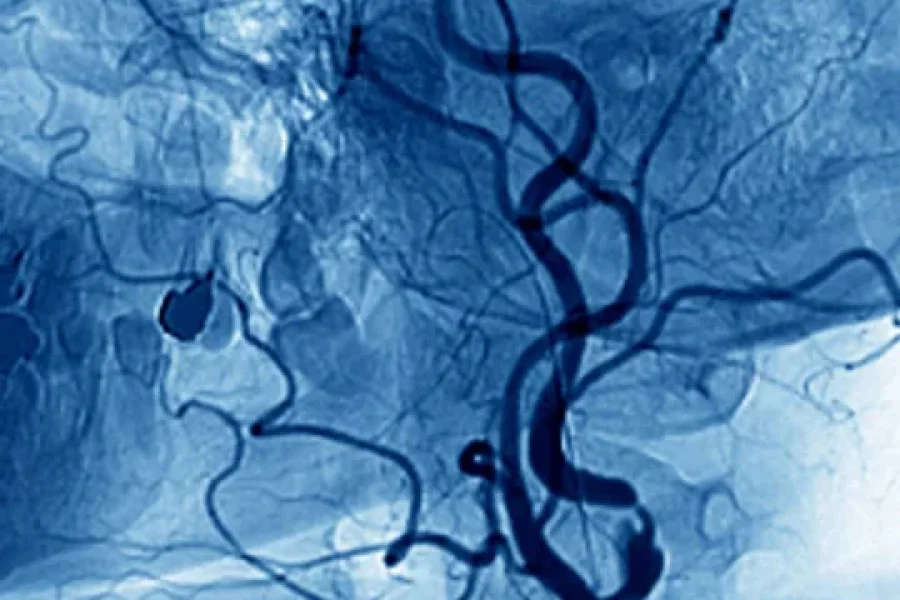

En las ultimas horas, se publicó un nuevo boletín epidemiológico por parte del Ministerio de Salud, donde se informó que hubo 270 muertos y 379.341 casos de dengue en lo que va del 2024. Estos números muestran que los contagios siguieron en aumento en la última semana, al igual que las muertes que también crecieron.

Según lo que informaron las autoridades del Gobierno, el mayor número de contagios sucedió en la región Centro, seguido por el NOA y el NEA. De estos, 871 casos fueron clasificados como dengue grave.

"Los casos acumulados hasta la semana 16 representan 3,25 veces más que lo registrado en el mismo período de la temporada anterior 2022/2023 y 9,24 veces más que lo registrado en el mismo período de 2019/2020, señaló.

Según las cifras que maneja el Ministerio de Salud, se registraron casos de dengue en todos los grupos de edad, aunque la mayor tasa de mortalidad se observó en los mayores de 80 años.